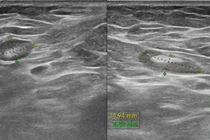

Phát hiện sớm ung thư vú ở người cao tuổi nhờ xét nghiệm giải phẫu bệnh Sức khoẻ 360 30/01/2026 14:16 Cụ bà 75 tuổi được chẩn đoán mắc ung thư vú xâm nhập sau khi xét nghiệm chính xác, giúp xây dựng phương pháp điều trị hiệu quả, giảm tác dụng phụ.